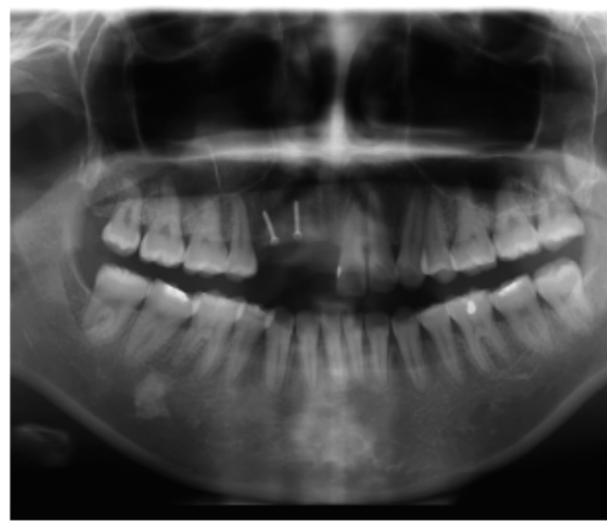

图3 术前全景片

图4 同一患者术后全景片